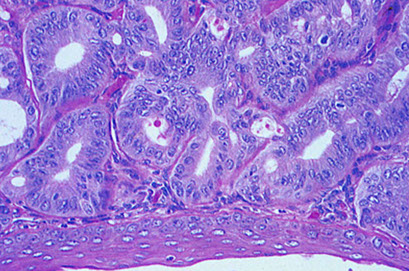

Condyloma acuminatum

Condyloma acuminatum - koilocytic atypia

Micro: blunt arborizing papillae, papillary squames, parakeratosis, koilocytes

- can see some dysplastic changes

- koilocytic atypia = nuclear enlargement, hyperchromasia, cytoplasmic perinuclear halo

Condyloma acuminatum is, by definition, a papillary proliferation with low-grade cytopathic features of HPV infection. The majority are caused by low-risk HPV types 6 and 11. Lesions within this spectrum are designated as LSIL, with the additional optional designation of condyloma in parentheses. Condylomas are common in external anogenital

areas and less frequent in the cervix and vagina. [1]

B9, HPV (usually subtypes 6 and 11) caused squamous prolif; usually multifocal